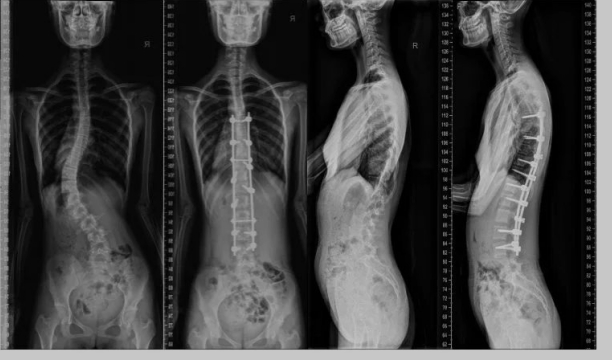

全嵴柱X线摄影通过正位、侧位投照,清晰显示颈椎、胸椎、腰椎和骶尾椎的整体形态与结构,主要适用于以下场景:

青少年特发性嵴柱侧弯的筛查和随访中,X线可量化侧弯角度(Cobb角),监测病情进展,是指导治疗的关键依据。

3. 术后随访与畸形矫正效果监测

嵴柱融合术后或支具治疗期间,X线可直观评估内固定位置及嵴柱力线变化。